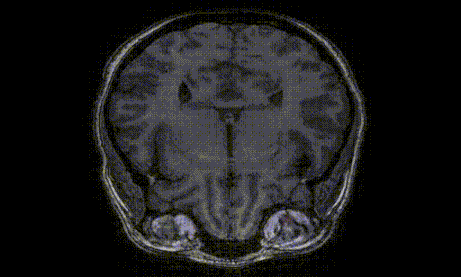

AI Superior nahm die Herausforderung an und konzentrierte sich auf die Analyse von MRT-Scans, um das Fett- und Muskelvolumen im menschlichen Auge abzuschätzen. Wir verwendeten modernste Deep-Learning-Techniken ein fortschrittliches Modell zu entwickeln, das in der Lage ist, Fett- und Muskelgewebe in jedem Schnitt eines MRT-Orbitalscans präzise zu segmentieren. Durch die Nutzung der Fähigkeiten des Modells konnten wir eine hochpräzise Volumenschätzung für die anatomischen Strukturen des Auges erreichen. Unser Deep-Learning-Modell wurde für die Verarbeitung verschiedener Ansichten des Auges, einschließlich koronal, sagittal und axial, entwickelt, um eine umfassende Analyse der Orbitalregion zu gewährleisten.